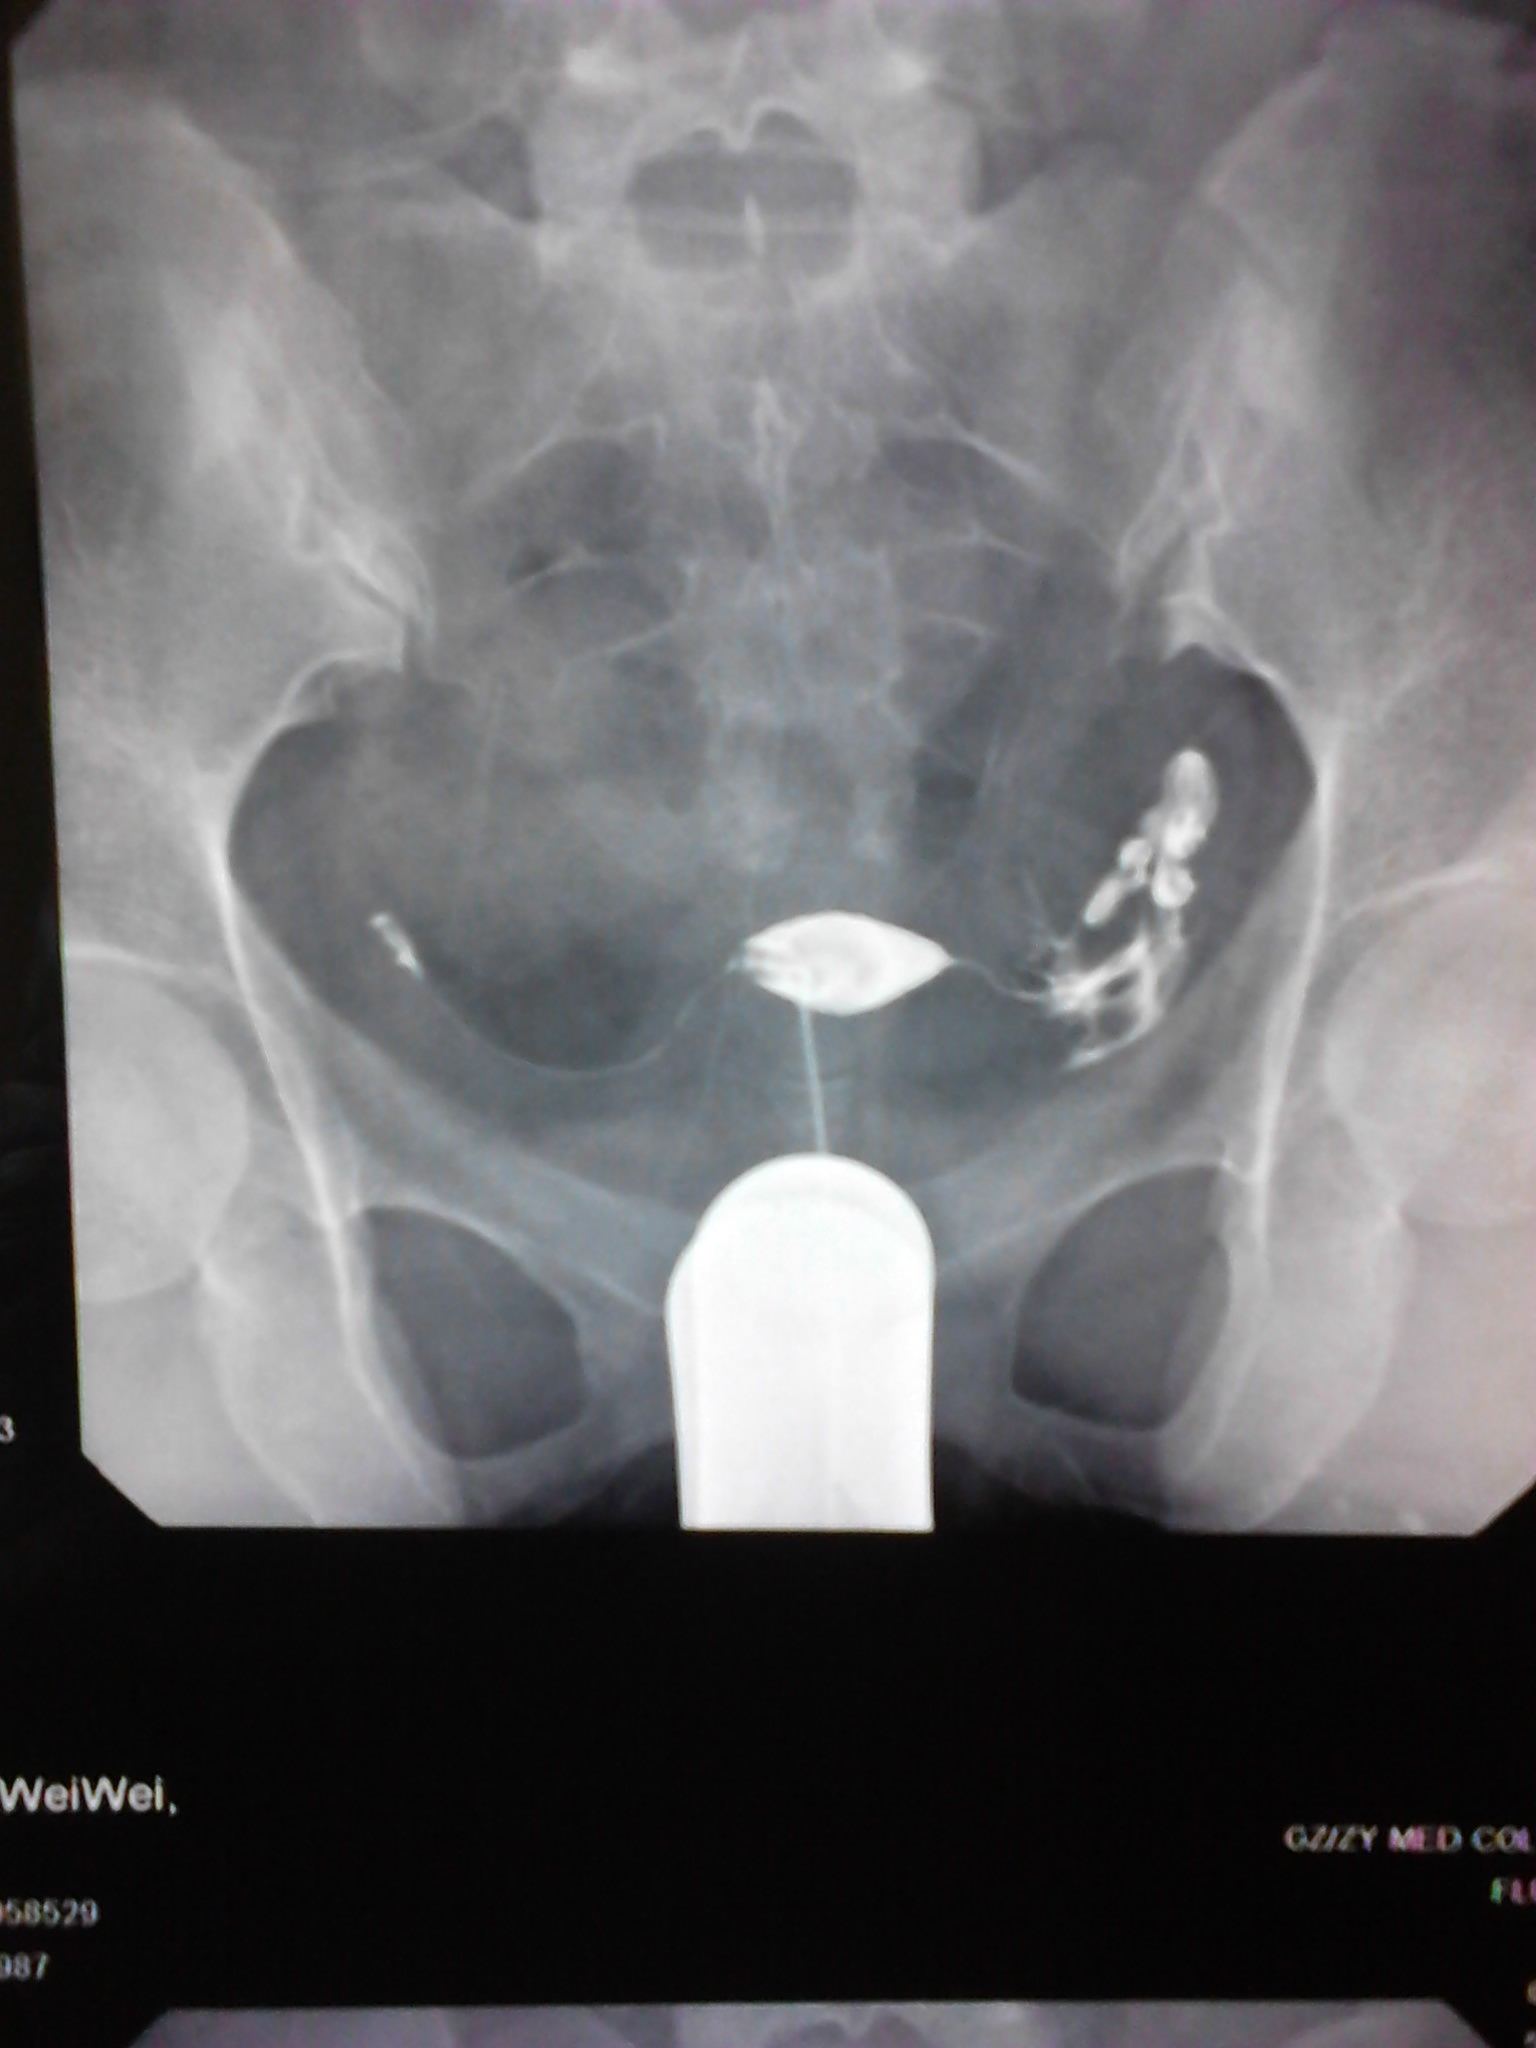

请大家看看造影的报告单,,,还有怀孕的机会吗? 患者信息:女 25岁 贵州 遵义 病情描述(发病时间、主要症状等):子宫腔大小.形态无明显异常.子宫粘膜面光滑整齐.宫腔内见气囊及气泡所致充盈缺损。双侧输卵管全程显影.双壶腹部粘膜皱襞增粗.双侧伞端呈锥状.其内造影剂呈喷射状进入腹腔.进入腹腔之造影剂弥散欠佳曾经治疗情况及是否有过敏、 遗传病 史:现在正在吃中药 点击展开 宇文令秋_1EAj 2012-06-17 13:32 满意回答 帮顶。。。。。。。。。。。。 欧阳弘新_SmTk 2012-06-17 13:51 宝宝知道提示您:回答为网友贡献,仅供参考。 相关问题 医生看看我的造影报告单 数字化X造影检查报告单还能生育吗? 做完造影这样的结果,次月跟第三个月会怀孕吗

患者信息:女 25岁 贵州 遵义 病情描述(发病时间、主要症状等):子宫腔大小.形态无明显异常.子宫粘膜面光滑整齐.宫腔内见气囊及气泡所致充盈缺损。双侧输卵管全程显影.双壶腹部粘膜皱襞增粗.双侧伞端呈锥状.其内造影剂呈喷射状进入腹腔.进入腹腔之造影剂弥散欠佳曾经治疗情况及是否有过敏、 遗传病 史:现在正在吃中药